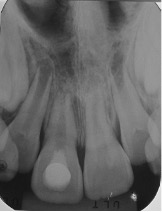

Se presenta el caso de un paciente de sexo femenino, de 8 años de edad. La paciente acudió acompañada con su padre al servicio de endodoncia del Instituto Nacional de Salud del Niño en Lima- Perú, con antecedentes de traumatismo dental, en sector antero superior y con dolor espontáneo. Al examen clínico intraoral, se evaluó que el diente 11 presentaba una ligera movilidad dental y al examen radiográfico se observó diente 11 no vital, ligero ensanchamiento del ligamento periodontal y desarrollo radicular en estadio 8 de Nolla (Figura 1 y 2). Se evaluó el caso y se realizó la explicación de las ventajas y desventajas del tratamiento de revascularización pulpar al padre de familia y se procedió a la firma del consentimiento informado para el tratamiento.

Figura 2: Radiografía periapical de diagnóstico.

Figura 3: Apertura cameral con piedra diamantada redonda a nivel de la cara palatina. Conductometría con lima K N° 35 en una longitud de 17 mm. Control radiográfico.